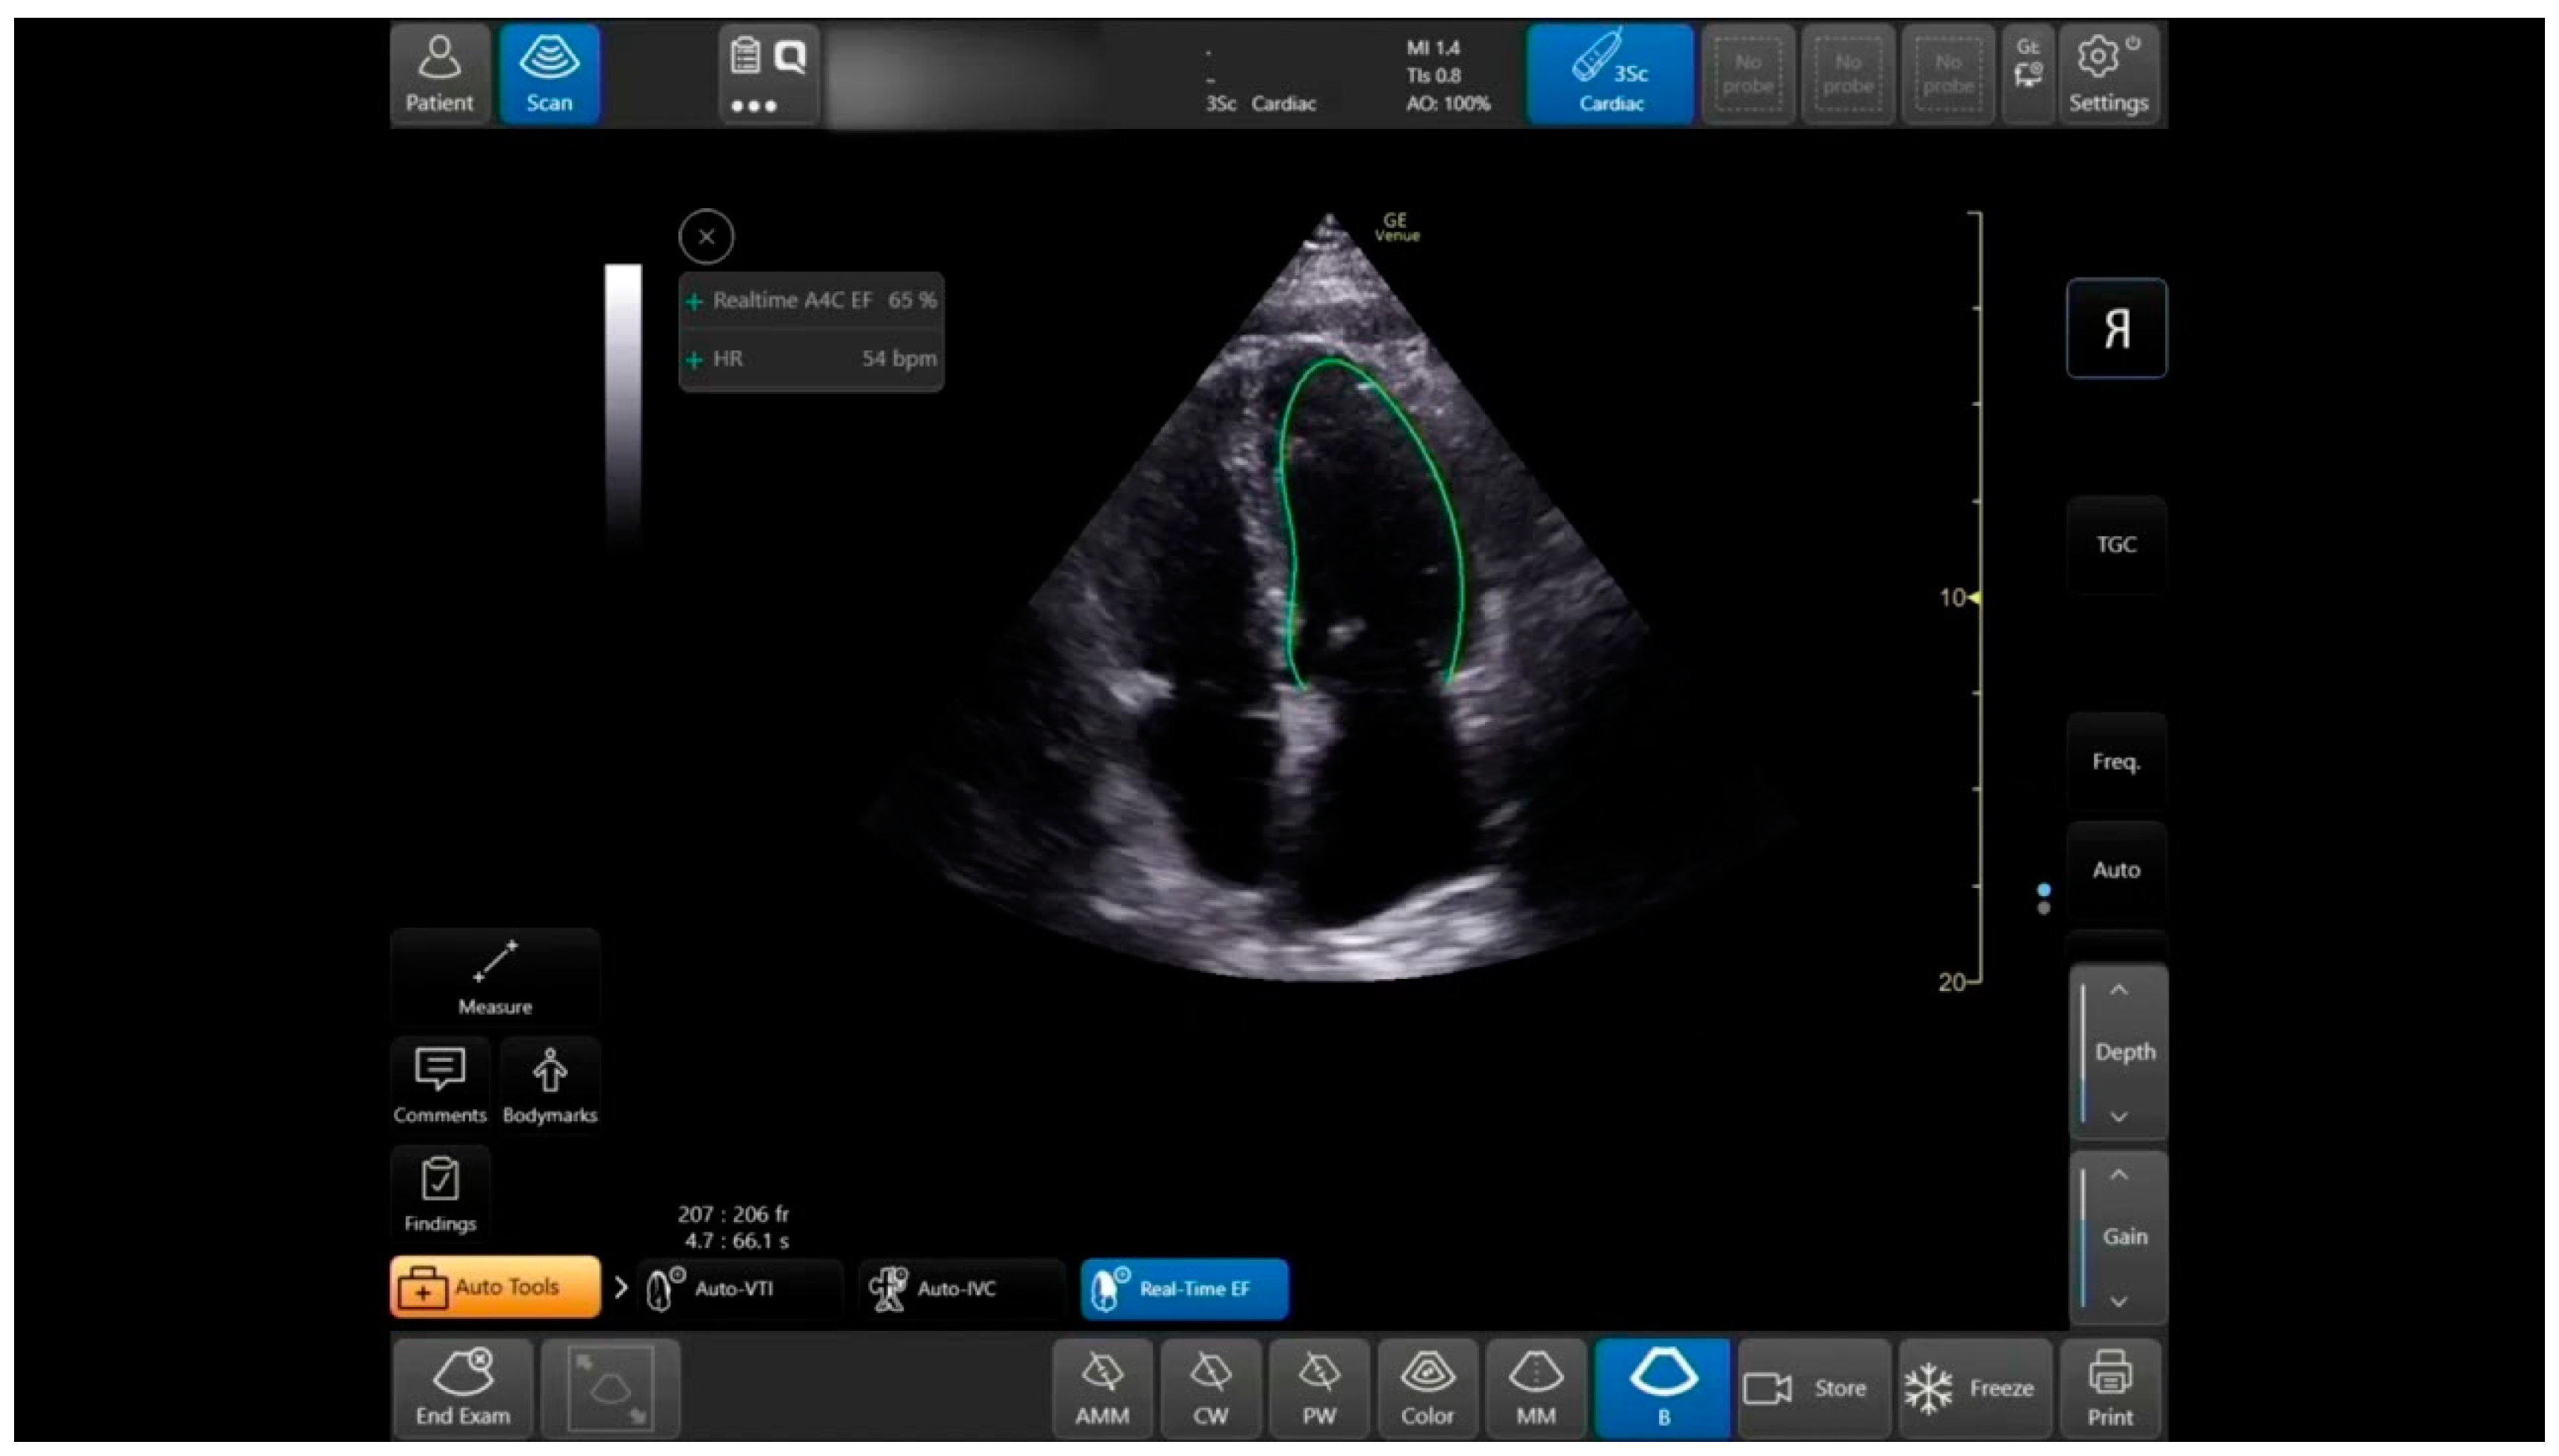

Figure 2.

Auto EF tool: in Apical-4-Chamber-View: auto LV outlining in systole and diastole, measurements, and data display.